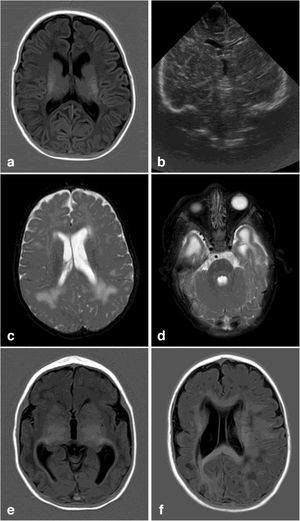

Brain MRIBrain MRI studies were performed in 29 patients (80%), at a mean age of 19.25 months (0.23-111.41). MRI detected alterations in 19 patients (70%); the most frequent alterations are detailed in Table 3 (Fig. 1).

Neuroimaging findings corresponding to the stages of the modified Noyola classification; (a and b) axial slices from T1-weighted brain MRI and transfontanellar ultrasound studies of a 43-day-old patient, scoring 1 on the classification. It shows the presence of a 6-mm germinolytic cyst in the left caudothalamic groove, as well as mild ventriculomegaly of the left lateral ventricle; (c and d) axial slices from T2-weighted brain MRI of a 2-month-old patient, with lesions scoring 2. Multicystic encephalopathy; (e) axial slice from a T1-weighted brain MRI scan of a 4-month-old patient, with a lesion scoring 3. Extensive loss of cortico-subcortical differentiation of the cortical perisylvian grey matter. Hypoplasia of the corpus callosum. Anomalies of neuronal migration and/or band heterotopia. Increased signal in the subcortical white matter of both temporal poles due to gliosis or malacia. Ventricles in the higher threshold of normality; (f) axial slice from a brain MRI FLAIR sequence of a 6-month-old patient, with a lesion scoring 3. Patchy signal in the white matter of both hemispheres and hemispheric asymmetry, with the right hemisphere being smaller in size and showing associated ventriculomegaly. Loss of cortico-subcortical differentiation and increased sulcation, compatible with polymicrogyria.